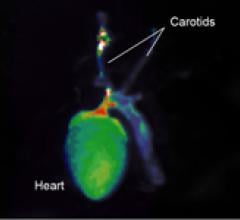

November 13, 2009 – A new imaging agent for measuring and monitoring cathepsin B activity associated with disease progression and therapeutic response in vivo will be released at the American Heart Association meeting in Orlando this weekend.